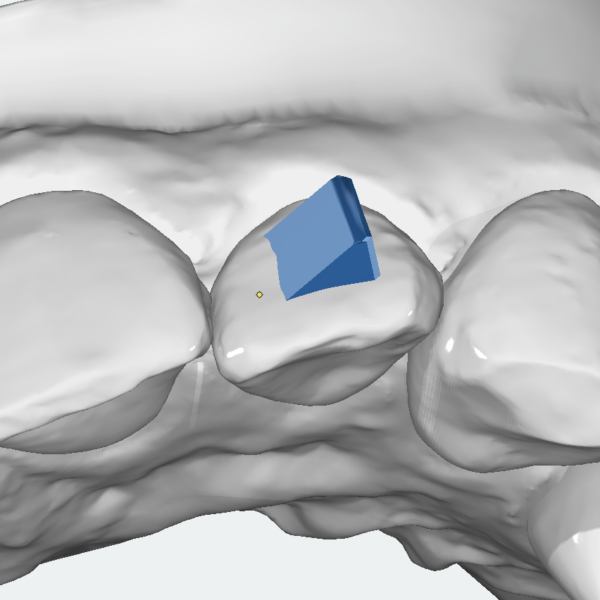

Aligner

Vertical Attachment

49,00 € excl. VAT Select options This product has multiple variants. The options may be chosen on the product page